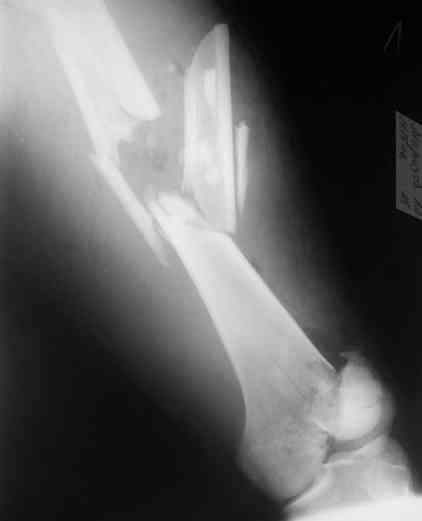

А в чем проблемы? Пример в приложении.

Насчет снимка Вами представленного - смотрится оч красиво, еще бы на функцию узнать...

I> Насчет снимка Вами представленного - смотрится оч красиво, еще бы на

I> функцию узнать...

В приложении функциональные снимки в 3 мес. и в 1 год.